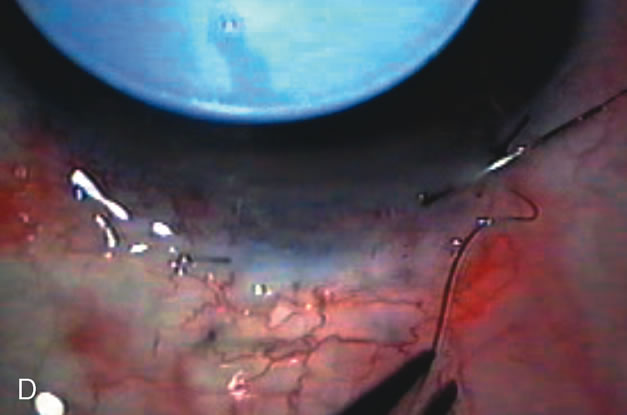

CATARACT EXTRACTION ALONE REDUCES IOP IN MOST EYES WITH ANGLE-CLOSURE GLAUCOMA

Uncomplicated cataract extraction substantially reduces IOP, along with the number of postoperative glaucoma medications in eyes with angle-closure glaucoma.146,147 When preoperative gonioscopy reveals PAS, along with adjacent areas of appositional closure, lens extraction alone in select cases may be a reasonable alternative to filtration surgery.148,149 Phacomorphic angle-closure disease due to enlargement of the lens with progressive angle crowding is eliminated following lens extraction. The width and depth of the anterior chamber angle in eyes with angle-closure glaucoma increases significantly after cataract extraction with IOL implantation and becomes similar to open-angle glaucoma and normal eyes.150,151 (Fig. 5). Combining phacoemulsification, IOL implantation, and limited goniosynechialysis is effective in the treatment of cataract and chronic angle-closure glaucoma.152 Phacoemulsification with implantation of a foldable IOL is more effective in reducing IOP and improving visual acuity than surgical peripheral iridectomy in eyes with acute angle-closure glaucoma.153

Fig. 5. Anterior chamber angle changes associated with lens extraction and PCIOL This 65-year-old Vietnamese woman has a long-standing history of chronic angle-closure glaucoma treated with laser peripheral iridectomy. The optic nerve demonstrated mild glaucomatous damage and IOP was moderately controlled on two antiglaucoma medications. The cataract was removed through temporal clear corneal phacoemulsification with foldable acrylic IOL. A. Symptomatic cataract in narrow-angle glaucoma eye with patent iridectomy. B. Intraoperative goniophotograph showing crowding of angle with increasing narrowness due to phacomorphic component. C. Intraoperative photograph showing temporal clear corneal approach with IOL in the capsular bag. D. Intraoperative goniophotograph demonstrating deepening of chamber angle following lens extraction. Proposed theories for IOP reduction following lens extraction with complete wound closure:

1. Anterior chamber deepening with improved access to trabecular meshwork

2. Increase in traction on the trabecular meshwork

3. Improved outflow facility mediated by an increase in prostaglandin release

4. Reduction in aqueous humor production

5. Atrophy of ciliary body processes

6. Goniosynechialysis due to intraoperative over deepening of AC with viscoelastic

7. Relief of undiagnosed pupil block